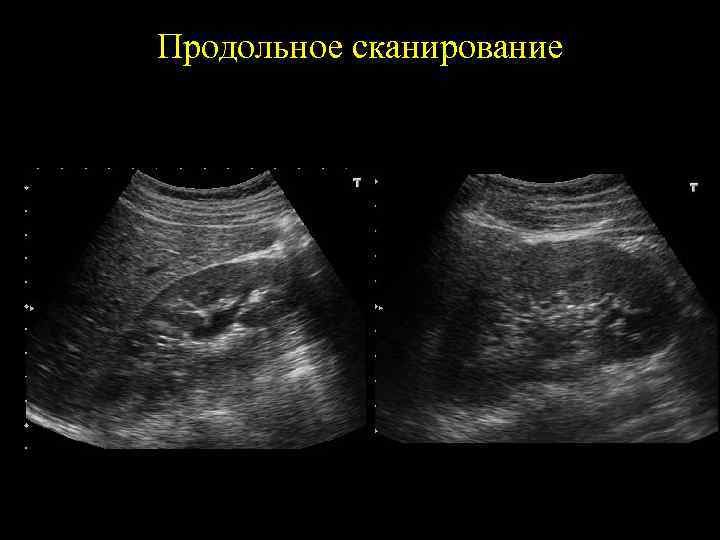

Продольное сканирование